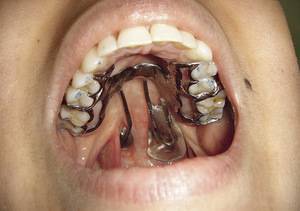

Когда волчья губа прооперирована, возвращение к нормальному режиму питания должно быть постепенным. В первые несколько суток пациенту внутривенно вводят специальные питательные растворы. Для правильного формирования верхнего неба после проведения операции устанавливают изготовленную по индивидуальным замерам пластину. Ее оставляют на 1 – 1,5 месяца и снимают на время еды и занятий по формированию правильной речи.

Весь этот период следует обязательно применять обтуратор, который отграничивает полость рта от носовой и препятствует забросу пищи в последнюю.

Если хирург запланировал двухэтапное лечение, то между пластиками должно будет пройти не менее года. Весь этот период следует обязательно применять обтуратор, который отграничивает полость рта от носовой и препятствует забросу пищи в последнюю.